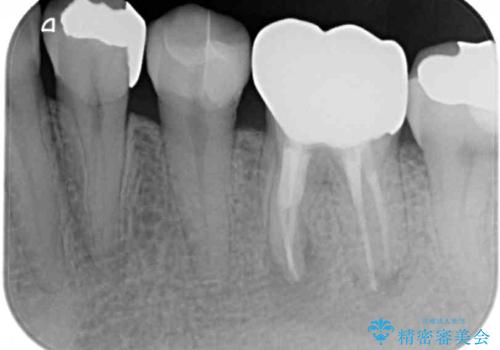

- 根っこの一部だけになった歯と咬むと痛みのある歯を気にして来院された患者様です。

上顎の歯根のみとなった歯は抜歯が必要であったので、抜歯を行い、インプラントあるいはブリッジのよる補綴治療を提案しました。

前後の歯は銀歯が装着されていたため、ブリッジによる補綴治療として、前後の歯もセラミックに置き換えることとしました。

下顎の根管治療がされた大臼歯は咬合時に痛みが認められたため、再度根管治療を行った後に補綴治療することとしました。